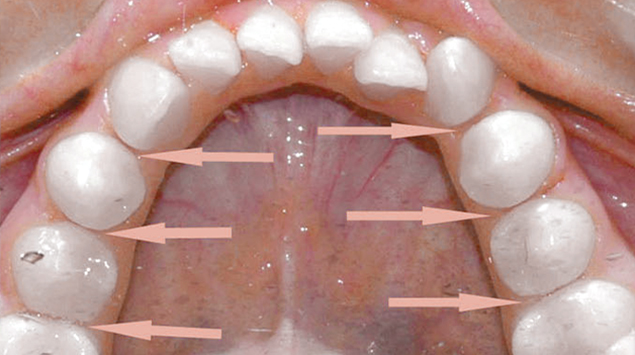

>   Stripping z zaokrągleniem i wygładzeniem brzegów zębów siev=cznych dolnych.